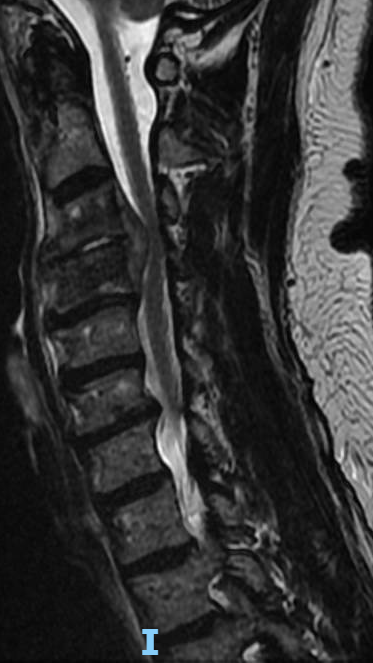

Update on the cervical epidural abscess case: Successful partial C4 corpectomy led to significant neurological recovery. Abscess was more phlegmon than liquid. Used fibular allograft for stability.